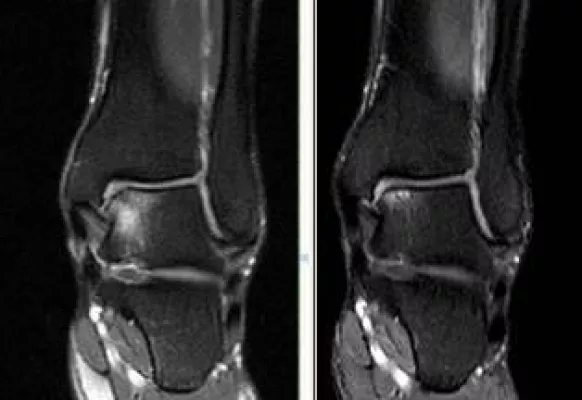

Dies war für eine Gruppe von sechs Ärzten im Jahre 1996 Grund genug, dafür zu sorgen, dass eine Druckkammer nach Freiburg kommt. Dr. med. Hellmuth Sümmerer, der leitende Arzt am Druckkammerzentrum Freiburg, ist von Anfang an dabei: "In über 45.000 durchgeführten Behandlungen hat sich die positive Wirkung der HBO bestätigt. In vielen Fällen konnten lästige Ohrgeräusche gemindert oder beseitigt werden. Neben dem Tinnitus bestand oft auch eine Hörminderung nach einem akuten Hörsturz. Auch hier haben Patienten oft ihr Gehör wieder gefunden oder zumindest verbessert. Geradezu erstaunlich ist die Wirkung des unter Überdruck eingeatmeten Sauerstoffs bei Knochenmarködemsyndromen", weiß der Mediziner zu berichten. In den meisten Fällen wird eine Gelenk-Prothese vermieden und Patienten erleben eine rasche Schmerzreduktion. Wunden in einem vorbestrahlten Gebiet heilen erst durch die HBO. "Selbst im Körperinnern lassen sich so Schäden an Blase und Enddarm zuverlässig heilen. Einschränkungen in der Lebensqualität werden beseitigt", so der Arzt.